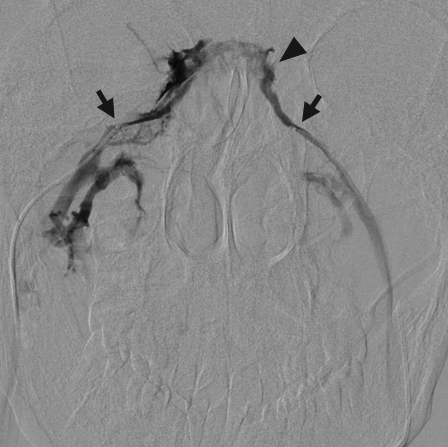

4.1. Bilateral Inferior Petrosal Sinus Sampling for Cushing’s Disease

- Deipolyi, A.R.; Alexander, B.; Rho, J.; Hirsch, J.A.; Oklu, R. Bilateral inferior petrosal sinus sampling using desmopressin or corticotropic-releasing hormone: A single-center experience. J. Neurointerv. Surg. 2014. [Google Scholar] [CrossRef] [PubMed]

- Deipolyi, A.; Bailin, A.; Hirsch, J.A.; Walker, T.G.; Oklu, R. Bilateral inferior petrosal sinus sampling: Experience in 327 patients. J. Neurointerv. Surg. 2016. [Google Scholar] [CrossRef]

- Oldfield, E.H.; Doppman, J.L.; Nieman, L.K.; Chrousos, G.P.; Miller, D.L.; Katz, D.A.; Cutler, G.B., Jr.; Loriaux, D.L. Petrosal sinus sampling with and without corticotropin-releasing hormone for the differential diagnosis of Cushing’s syndrome. N. Engl. J. Med. 1991, 325, 897–905. [Google Scholar] [CrossRef] [PubMed]